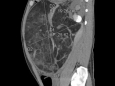

该技术通过在超声引导下经皮经肝穿刺建立进入胆道的微创通道,利用胆道镜直视下进行精准碎石与取石,尤其适用于肝内胆管结石位置深在、分布广泛、既往多次手术后解剖结构复杂、常规内镜或开腹手术难以处理的棘手病例。

据介绍,PTCS技术通过在超声引导下经皮经肝穿刺建立进入胆道的微创通道,利用胆道镜直视下进行精准碎石与取石,尤其适用于肝内胆管结石位置深在、分布广泛、既往多次手术后解剖结构复杂、常规内镜或开腹手术难以处理的棘手病例。